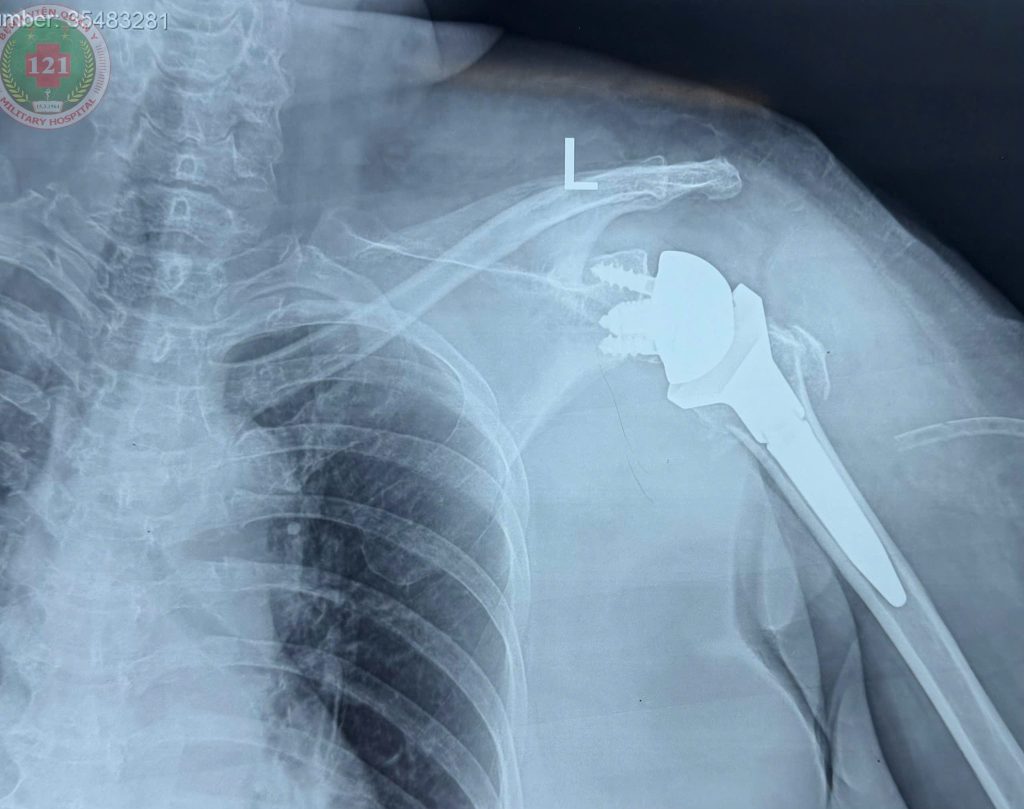

Bệnh nhân nhập viện cách đây 10 ngày sau một vụ tai nạn giao thông, trong tình trạng cánh tay trái sưng nề, biến dạng, vận động hạn chế, đồng thời có đa tổn thương tại cổ chân và bàn chân. Bệnh nhân được chụp Cắt lớp vi tính dựng hình thấy đầu trên xương cánh tay bị vỡ nát, chỏm vai vỡ vụn thành nhiều mảnh. Sau khi thăm khám và hội chẩn, bệnh nhân được chỉ định phẫu thuật thay khớp vai toàn phần.

Nhờ sự phối hợp chặt chẽ giữa đội ngũ bác sĩ Bệnh viện Quân y 121 và sự hỗ trợ kỹ thuật từ Bệnh viện Chấn thương chỉnh hình TP. Hồ Chí Minh, sau hơn 2 giờ phẫu thuật, ca mổ đã thành công tốt đẹp. Sau phẫu thuật, bệnh nhân có tiên lượng phục hồi vận động tốt, sẽ sớm trở lại với cuộc sống thường ngày.